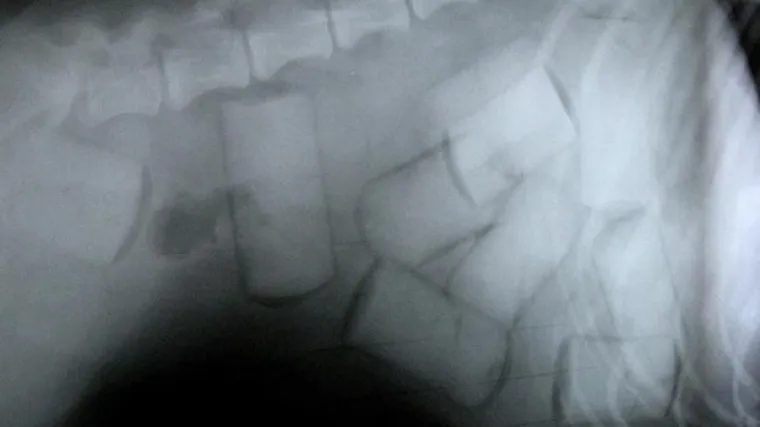

Dileru eksplodirao kokain u želucu

Jedan je muškarac iz Srbije preminuo nakon što je dovezen u bolnicu bez znakova života, a autopsijom je utvrđeno kako je umro od puknuća kapsule kokaina koju je imao u želucu.

Jedan je muškarac iz Srbije preminuo nakon što je dovezen u bolnicu bez znakova života, a autopsijom je utvrđeno kako je umro od puknuća kapsule kokaina koju je imao u želucu. U njegovom je želucu pronađeno čak 66 kapsula s otprilike 700 grama kokaina, piše Blic.